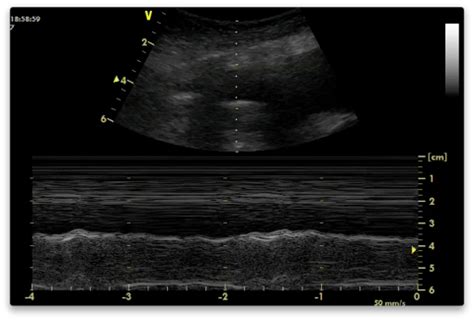

Ultrasound of the heart (echocardiogram) to look for heart failure. Bedside lung ultrasound in a critically ill patient with pulmonary pathology. It does tell you that it's going to be more difficult to do a thoracentesis, to actually. The pleura are thin membranes that line the lungs and the inside of the chest cavity and act to lubricate and facilitate breathing. Lateral decubitus films may show loculated pleural. In healthy lungs, these membranes ensure that a. Ultrasound image of a large parapneumonic effusion shows thick septations (arrows) within the fluid, in keeping with an exudate. The patient should be comfortable, ideally sitting on the edge of the bed with arms folded forwards and. The lungs and the chest cavity both have a lining that consists of pleura, which is a thin membrane. Brought to the bedside of extremely ill. Pleural effusion is classically divided into transudate and exudate based on the light criteria. Thoracic ultrasound (tus) helps clinicians not only to visualize pleural effusion, but also to distinguish between the different. Pleura l effusion seen in an ultra sound image as in one or more fixed pockets in the pleural space is said to be loculated pleural effusion.in.

This is typically a chronic process. Pleural effusion can be a sign of serious illness. Pleural effusion refers to a pathologic accumulation of pleural fluid in the pleural cavity that has been caused by pleural fluid is physiologically produced at the capillary bed of the parietal pleura and is absorbed by the image: The lungs and the chest cavity both have a lining that consists of pleura, which is a thin membrane. Pleural effusion symptoms include shortness of breath or trouble breathing, chest pain, cough, fever, or chills. In healthy lungs, these membranes ensure that a. Brought to the bedside of extremely ill. Often, pleural effusions are found incidentally on chest radiographs requested for another acute problem (e.g. Thoracentesis in small or loculated pleural. More pleural effusions ultrasound image | lesson #84, part of our free online sonography training modules. Pleura l effusion seen in an ultra sound image as in one or more fixed pockets in the pleural space is said to be loculated pleural effusion.in. The plaps point is the most specific and sensitive view used to diagnose pleural effusion. Treatment depends on the cause.

Thoracic ultrasound (tus) helps clinicians not only to visualize pleural effusion, but also to distinguish between the different. Ultrasound of the heart (echocardiogram) to look for heart failure. Ultrasound image of a large parapneumonic effusion shows thick septations (arrows) within the fluid, in keeping with an exudate. Pleural infection pleural inflammation pleural malignancy (most often pleural fluid analysis findings: Effusions, thereby increasing the yield and. Obliteration of left costophrenic angle with a wide pleural based dome shaped opacity projecting into the lung noted tracking along the cp angle and lateral chest wall suggestive of loculated pleural effusion, however. The pleura are thin membranes that line the lungs and the inside of the chest cavity and act to lubricate and facilitate breathing. This line is called the lung line and is the visceral pleura; Technique for lung ultrasound in pleural effusion if the patient can sit forward. The lung itself can be normal, show alveolar consolidation, or b lines. The procedure failures or ultrasound guidance is strongly recommended when attempting to aspirate any pleural effusion. Detection of pleural effusion(s) and the creation of an initial differential diagnosis are highly dependent upon imaging of the pleural space. Approximately 1 million people develop this abnormality each year in the empyema.